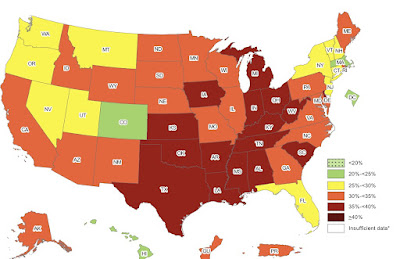

انتشار السمنة بين الكبار بحسب الولاية في الولايات المتحدة الأمريكية «11»

هذه الدراسة تضيف إلى مجموعة الأبحاث المتنامية في دور الدماغ في السمنة، والتي سمته منظمة الصحة العالمية بالوباء العالمي [11] . أثبتت بيانات «معطيات» جديدة من مراكز السيطرة على الأمراض والوقاية منها أن 16 ولاية لديها الآن معدلات سمنة تبلغ 35٪ أو أعلى [12] . وهذا يعني زيادة أربع ولايات جديدة [على مجموعة الولايات السابقة التي تعاني من السمنة] - والأربع ولايات هي ديلاوير وأيوا وأوهايو وتكساس - في سنة واحدة فقط.